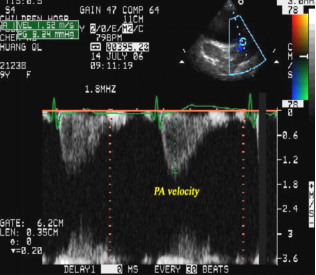

胸骨旁主动脉短轴观:

肺动脉内湍流频谱,

表明肺血流量增多,肺动脉瓣相对狭窄

(间接征象)

脉冲多普勒:

肺动脉瓣口流速增快,